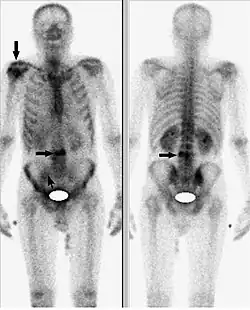

Исследование начинается с внутривенного введения 99mTc-золедроновая кислота (Резоскан) с активностью 5 МБк/кг с последующим сканированием спустя 1-3 часа после инъекции, с обязательным предварительным опорожнением мочевого пузыря. Равномерное поглощение вещества костями обычно говорит о норме. Фокальное поглощение (локальное поглощение, отличающееся по интенсивности от такового в соседней кости) может свидетельствовать об аномалиях. Если фокальное поглощение интенсивнее, чем поглощение в соседней кости, это может быть признаком артрита, перелома или наличия метастазов. Менее интенсивное, чем в соседних костях, фокальное поглощение указывает на возможный некроз опухоли, лизис новообразования или последствия лучевой терапии. Размеры ни одной из коммерчески доступных гамма-камер не позволяют получить изображение всего тела взрослого человека без перемещения камеры или пациента. Таким образом, сканирование скелета проводится с помощью перемещения камеры вдоль длинной оси пациента или перемещения пациента вдоль камеры. Для сканирования скелета детекторы размещают в положениях 90° и 270°, пациент лежит на спине ногами по направлению к гентри. Затем стол вместе с пациентом перемещается в точку начала сканирования, в которой голова пациента находится в поле зрения камеры. Во время исследования пациент и стол перемещаются таким образом, что сканирование идёт с головы до ног. Получение изображений всего тела («whole body»), которые представляют собой относительные значения поглощения радиомаркера в области головы, груди, брюшной полости и ног, требует точного кодирования и сопоставления параметров сканирования и движения пациента. Большинство таких процедур проводится с помощью гамма-камер, содержащих по два детектора, так что передняя и задняя проекции снимаются одновременно.

Однофотонная эмиссионная компьютерная томография[3] (ОФЭКТ) с помощью 99mTc-золедроновой кислоты — это дополнительное исследование, проводящееся для лучшей оценки и локализации возможных патологий, выявленных ранее с помощью планарного исследования («whole body»). Подготовка пациента к ОФЭКТ-исследованию скелета аналогична подготовке при планарном исследовании. Если ОФЭКТ проводится сразу после планарном исследования, то дополнительного введения 99mTc-золедроновая кислота не требуется. Параметры для получения данных с помощью ОФЭКТ-системы с двумя камерами, расположенными по отношению друг к другу под углом 180°, и при пошаговом сканировании следующие:

При патологии костей появляются фокусы поглощения, которые выше или ниже нормы.

- для выявления и идентификации литических, смешанных и бластных метастазов в скелете, при злокачественных опухолях различного происхождения и распространённости;

Наиболее значимым критерием проведения остеосцинтиграфии с помощью 99mTc-золедроновая кислота (Резоскан) является поиск метастатических поражений скелета. Качество проводимого исследования, главным образом, зависит от носителя и его тропности к костной ткани. Как уже отмечалось выше, в настоящее время, применяют дифосфонаты, где золедроновая кислота является максимально чувствительной к очагам повышенной резорбции кости.